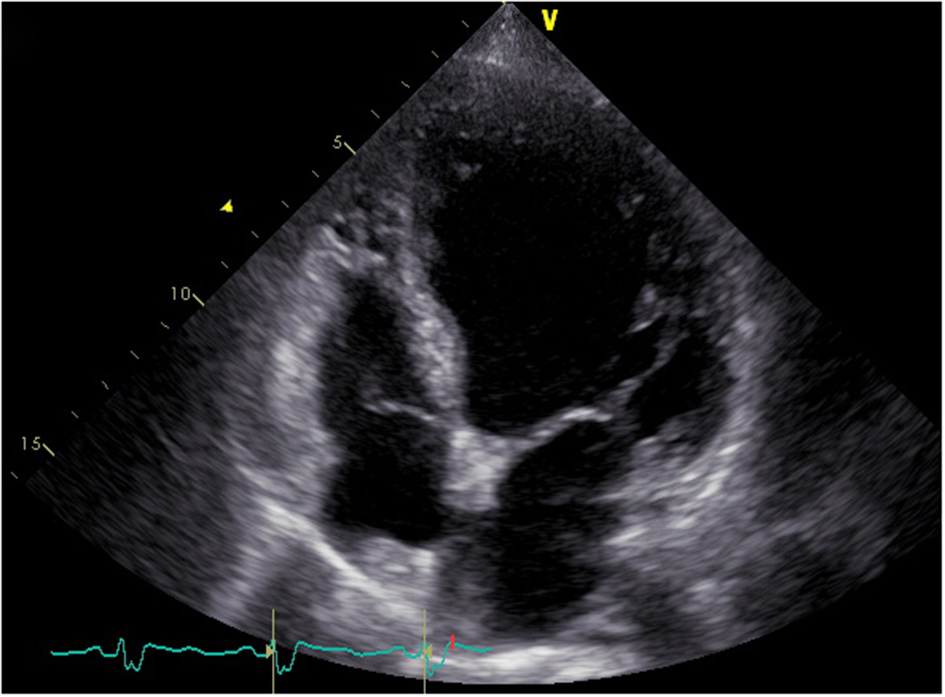

In April 2018, a 68-year-old woman was referred to our center presenting with rapidly progressive dyspnea. During the previous 12 years, she had been hospitalized more than 100 times for severe heart failure and shock. These episodes were so dramatic that even transient anger could cause acute-onset of dyspnea and shock. Additionally, she reported fatigue, dizziness, anorexia, vomiting, and a 5-kg weight loss during 1 month. Her past medical history revealed a 15-year history of seasonal dermatitis, intermittently treated with oral dexamethasone. On physical examination, she was notable for pallor, hypotension (86/46 mmHg), pulmonary rales, and lower extremities swelling. Laboratory tests were unremarkable except for hyponatremia (Na: 128 mmol/L) and elevated N-terminal pro-B-type natriuretic peptide (NT-Pro BNP: 6,343 pg/mL). In addition, her free thyroxine (FT4) and triiodothyronine (FT3) levels were normal, while thyroid-stimulating hormone (TSH) level was increased (TSH: 11.04 mIU/L, normal TSH: 0.38–5.57 mIU/L). Her electrocardiogram revealed sinus rhythm with complete left bundle branch block (Figure 1). Transthoracic echocardiogram showed a dilated and severely hypokinetic left ventricle (LV 68 mm) with an ejection fraction (EF) of 33% (Figure 2), while coronary angiography revealed no significant coronary artery disease. Therefore, she was diagnosed with idiopathic dilated cardiomyopathy (DCM). However, 3 days after receiving standard heart failure and antishock treatment all her symptoms and signs remained.

FIGURE 2

www.frontiersin.org

Figure 2. Four-chamber echocardiogram showing a dilated left ventricle.

In addition to previous normal saline, torasemide (10 mg i.v. twice daily), spironolactone (20 mg once daily), digoxin (0.125 mg once daily), dopamine (10 μg/kg/min), and norepinephrine infusion (0.3 μg/kg/min), hydrocortisone (50 mg) was administered intravenously every 6 h. Within 4 days, her blood pressure normalized, physical activity improved, edema resolved completely, and hyponatremia was corrected. Following that, normal saline and norepinephrine were discontinued, dopamine and intravenous hydrocortisone were gradually withdrawn in the next few days, and an oral hydrocortisone maintenance dose was instituted. Two weeks later, she recovered and was discharged on digoxin (0.125 mg once daily), bisoprolol (1.25 mg once daily), spironolactone (20 mg once daily), torasemide (10 mg once daily), and hydrocortisone (12.5 mg + 7.5 mg + 5.0 mg). During the follow-up period, her compliance and persistence with these medications remained excellent, and she had never experienced any episodes of heart failure and shock. We had tried to initiate low-dose candesartan (1 mg once daily) several times but failed, because it caused hypotension. Echocardiogram performed 18 months following hydrocortisone replacement therapy revealed mild improvement in EF and LV reverse remodeling (EF 35%, LV 64 mm), while her complete left bundle branch block remained. Unfortunately, she refused the implantation of defibrillator with cardiac resynchronization therapy (CRT-D) and died of sudden cardiac death in May 2020.